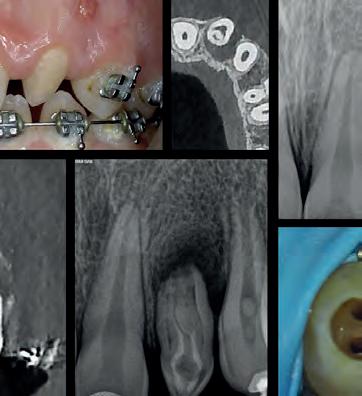

Endodoncia Clínica y Biocerámicos: Soluciones Prácticas de lo Simple a lo Complejo

Endodoncia Clínica y Biocerámicos: Soluciones

Prácticas de lo Simple a lo Complejo

PROGRAMA

VIERNES 12 | 15:30 - 20:00 (Teoría)

• Acceso al sistema de conductos e instrumentación rotatoria.

• Materiales biocerámicos: cementos selladores y reparadores.

• Aplicaciones clínicas de los biocerámicos: terapia pulpar vital y diente con ápice abierto.

• Complicaciones en endodoncia: perforaciones, escalones, fisuras, sobreinstrumentación...

• Diagnóstico y tratamiento de complicaciones en traumatología dental y reabsorciones.

SÁBADO 13 | 09:00 - 13:30 (Práctica)*

• Prácticas de obturación y reparación con cementos biocerámicos TotalFill (FKG Dentaire).